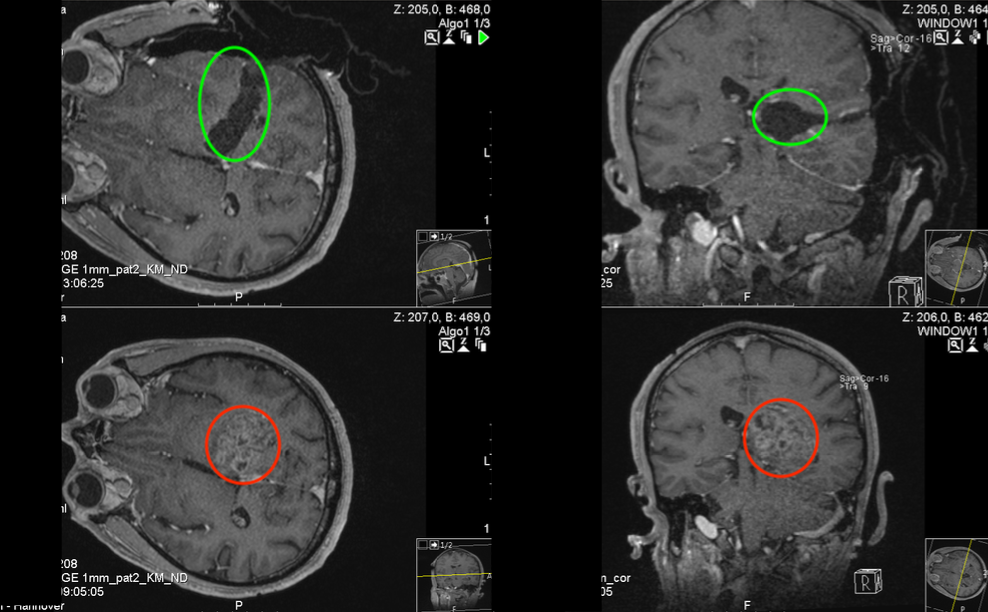

在5-ALA荧光、术中神经导航和术中MRI辅助手术,通过左侧顶枕枕骨开颅术和显微外科肿瘤全切手术,手术顺利,无手术并发症。

术中磁共振检查,显示肿瘤准确全切(红色表示切除前,绿色表示切除后)